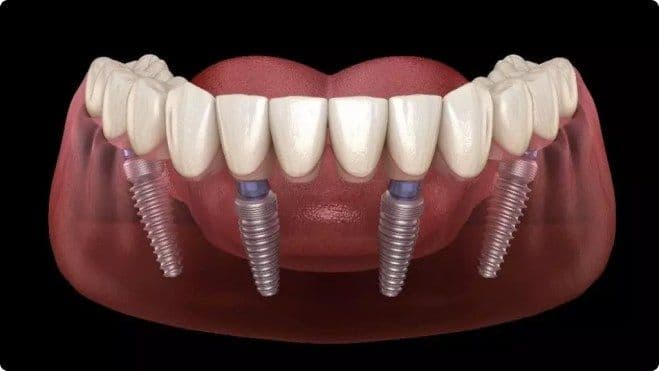

The All-on-4 dental implant procedure is a revolutionary technique that allows for the placement of a full arch of teeth using only four dental implants.

✅ Ideal for patients missing all teeth in one or both jaws

✅ Provides a fixed, permanent, and stable solution

✅ Eliminates the need for removable dentures